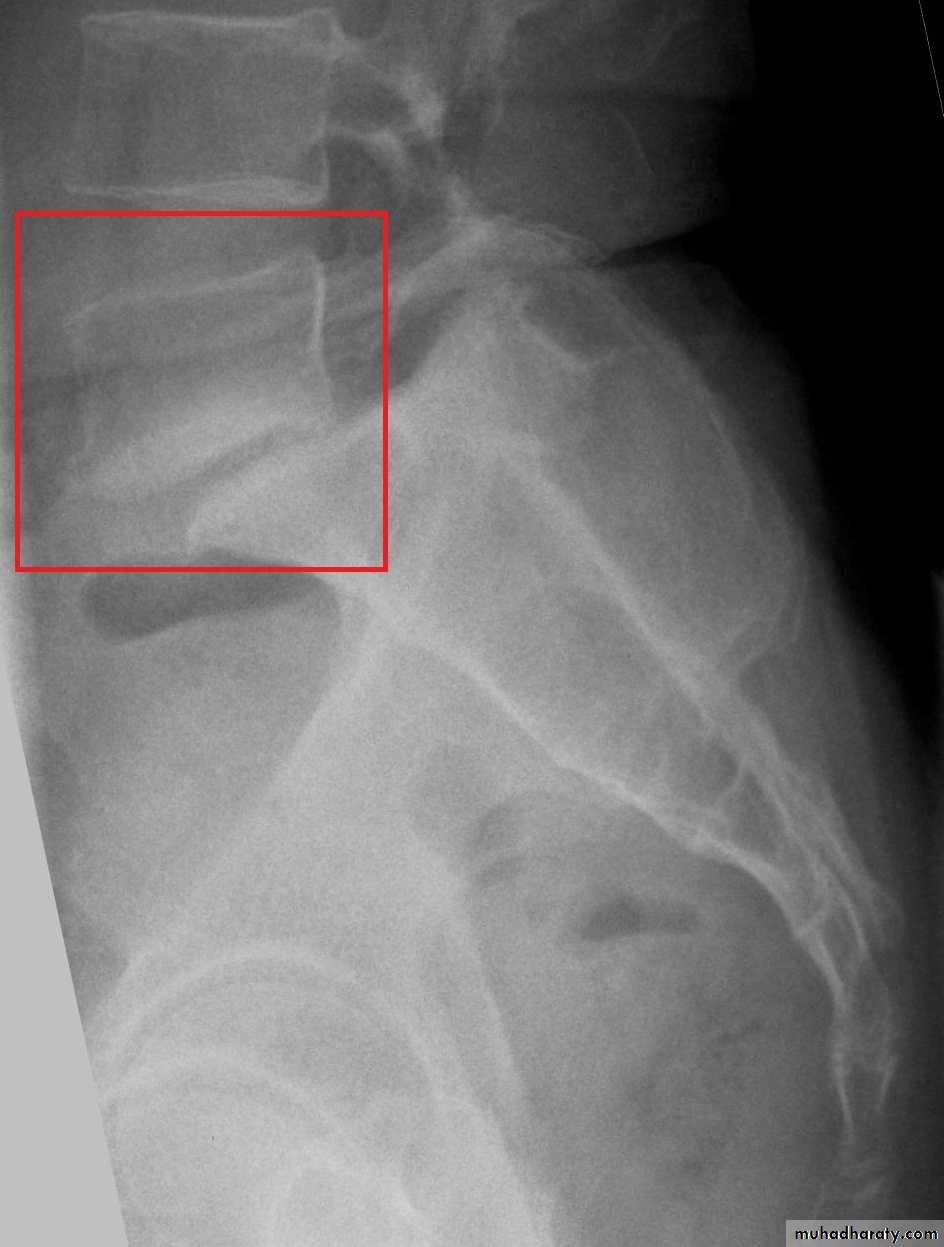

Spondylolisthesis means forward translation of one segment of the spine upon another. The shift is nearly always between L4 and L5, or between L5 and the sacrum.Backward translation is called retrolisthesis.

Pathology:In the common lytic type, the pars interarticularis on both sides is disrupted (spondylolysis), leaving the posterior arch separated from the vertebral body anteriorly; the gap is occupied by fibrous tissue. With stress, spondylolisthesis developed.

The degree of slip is measured by the amount of overlap of adjacent vertebral bodies and is usually expressed as a percentage. With slipping there will be spinal stenosis.

X-ray:Lateral views show the forward shift of the vertebra above on the vertebra below.

The gap in the pars interarticularis is best seen in the oblique views.

CT-scan and MRI are helpful.